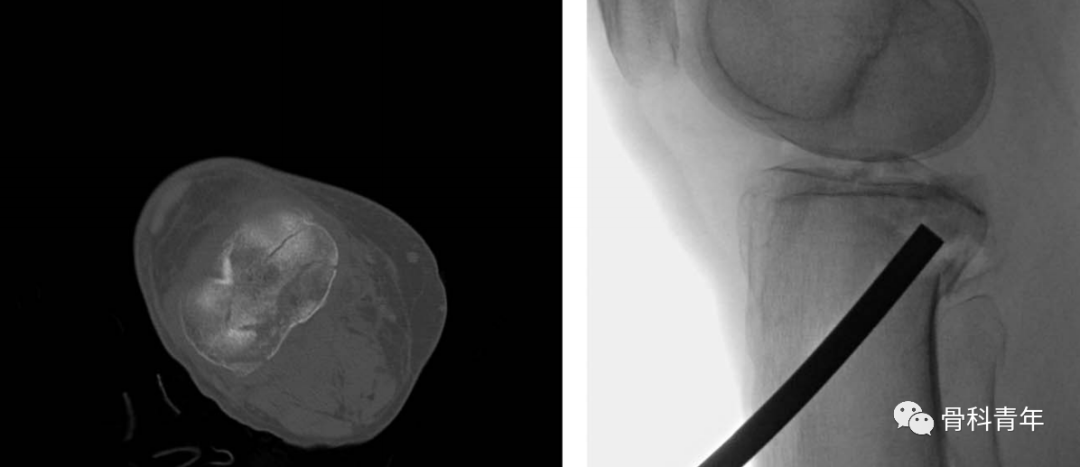

步骤2:在直视下,通过前外侧骨皮质开窗,钉棒技术复位后方劈裂塌陷骨块,并请过前向后克氏针临时固定。复位后干骺端骨缺损结构性植骨。

步骤3:常规后内侧切口,在膝关节屈曲20°下,显露腓肠肌内侧头并将其向后牵拉,沿着胫骨后柱骨面边缘松解软组织,预留钢板放置空间。在屈曲状态下可确保膝关节血管神经松弛,上述操作在血管神经束的前方进行。